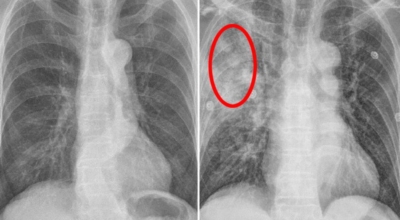

4. 폐렴 진단: 어떻게 폐렴을 확인할 수 있을까요?

폐렴은 증상만으로는 정확하게 진단하기 어려우므로, 다음과 같은 검사를 통해 진단합니다.

- 흉부 X선 촬영: 폐의 염증 부위를 확인하는 가장 기본적인 검사입니다.